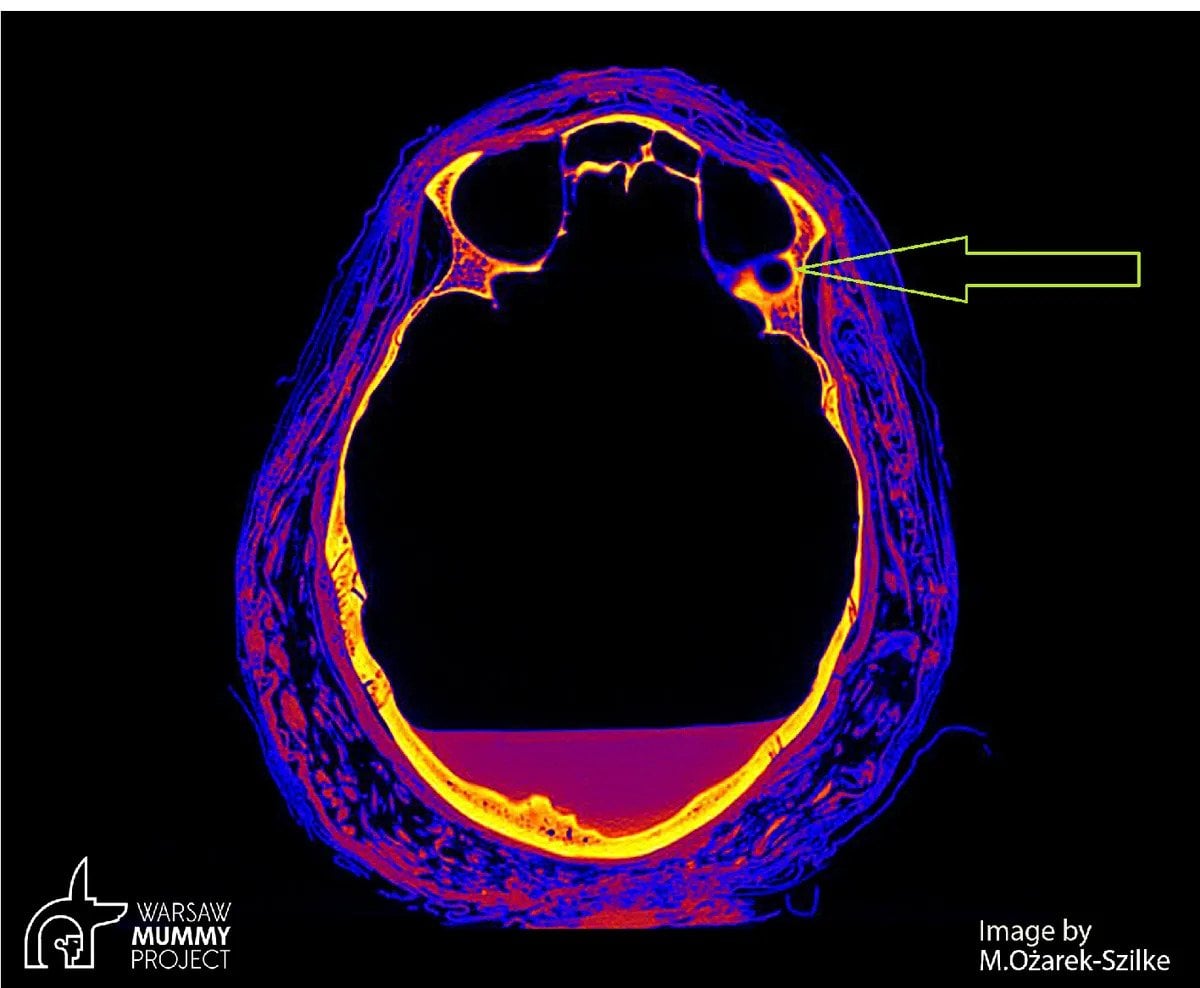

Nie było natomiast jasne, w jakich okolicznościach doszło do śmierci kobiety. Aby odpowiedzieć na to pytanie, archeolodzy wykonali tomografię komputerową jej czaszki. Skany wykazały istnienie nietypowych sygnatur w kości, wskazujących na możliwość chorowania kobiety na raka. Jednym z najbardziej prawdopodobnych kandydatów wydaje się rak nosogardła – rzadko spotykany, lecz występujący również współcześnie.

Na tomografii komputerowej, w kości za lewym oczodołem, widać niewielką zmianę patologiczną, o średnicy około 7 milimetrów, okrągłą strukturę otaczającą pustą przestrzeń. Jest to najprawdopodobniej zmiana wykonana przez guz, być może miejsce przerzutowe. […] Ponadto w kościach twarzy znajdują się duże ubytki, w tym w jamie nosowej, zatokach szczękowych, części podniebiennej kości szczękowych. wyjaśnia Wojciech Ejsmond z Warsaw Mummy Project